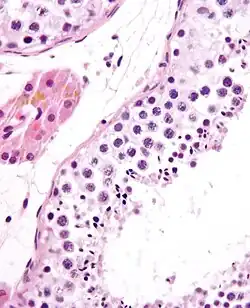

![]() Seminiferous tubule with maturing sperm. H&E stain. | |

Spermatogenesis starts in the bottom part of seminiferous tubes and, progressively, cells go deeper into tubes and moving along it until mature spermatozoa reaches the lumen, where mature spermatozoa are deposited. The division happens asynchronically; if the tube is cut transversally one could observe different maturation states. A group of cells with different maturation states that are being generated at the same time is called a spermatogenic wave.[5]